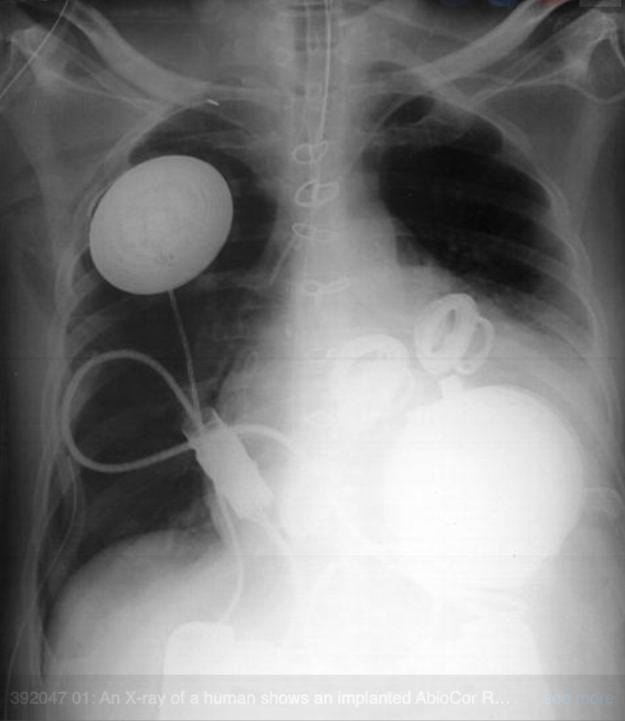

5. Аппарат искусственного сердца AbioCor